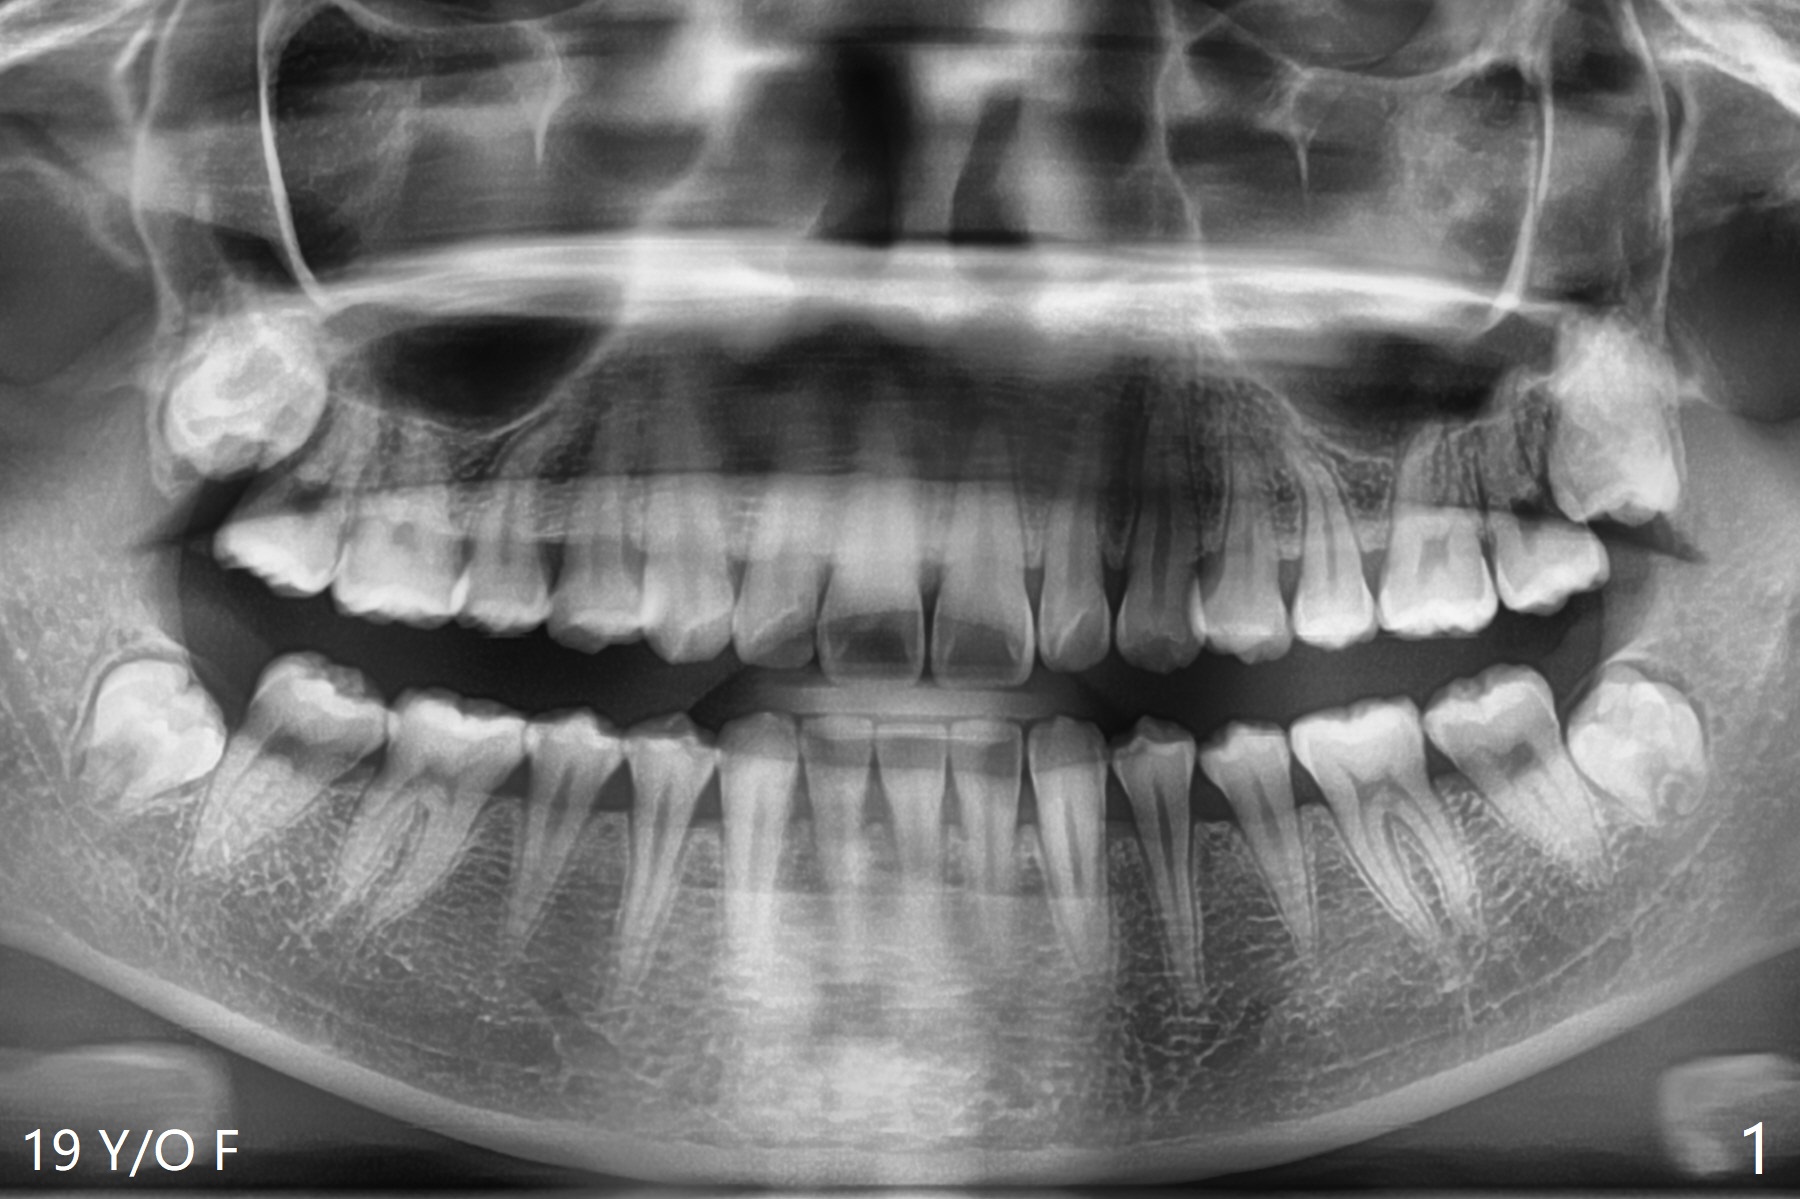

19岁女想在上大学前一次性拔除四个智齿(图一),术前口角涂抗病毒药粉(Acyclovir)凡士林(图二)。图三显示右上磨牙区,L型切口将做在第二磨牙远中(图四),光注射上牙槽后神经止痛还不够,第二磨牙上方还必须使用利多卡因(含肾上腺素1:50,000,而不是1:100,000,止血效果好)。上颌智齿区骨质松软,不必用手机钻头切骨产生purchase point,可以使用Crane Pick插入智齿近中(图五)慢慢撬动牙齿,防止大块上颌结节骨折。如果觉得杠杆作用不够,使用Potts(图六)让牙齿脱位。图七显示右下智齿区,由于舌神经位于牙槽嵴舌侧粘膜下,切口不要超过牙槽嵴(图八)。图九显示术后即刻,下颌智齿牙槽窝密度不同。原来右下牙槽窝放置骨胶原塞,而左下胶原塞。